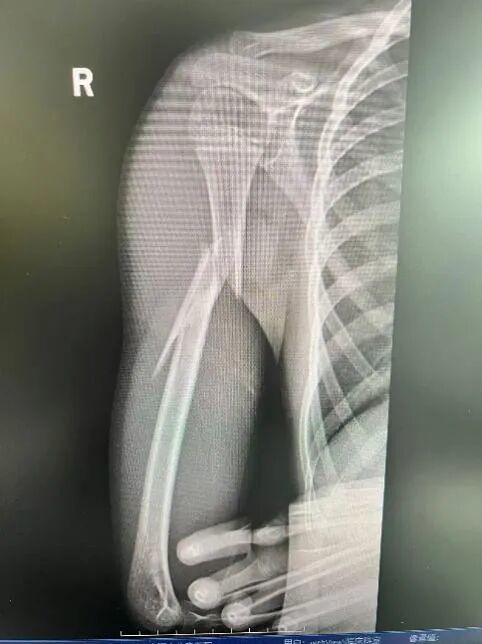

经急诊X光检查,乐乐被确诊为“右肱骨干粉碎性骨折”。肱骨是上臂最粗壮的骨头,此类骨折通常伴随剧烈的疼痛和明显的畸形,还容易造成桡神经损伤,该神经一旦损伤,会造成永久性的功能障碍,包括无法抬手腕和翘拇指。